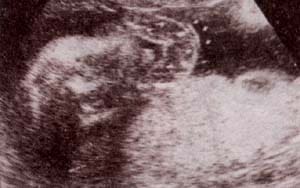

fig. 61. anencefalia. 14 semanas.ausencia de calota observándose un tejido cerebrovascular expuesto. no hay masa encefálica. |